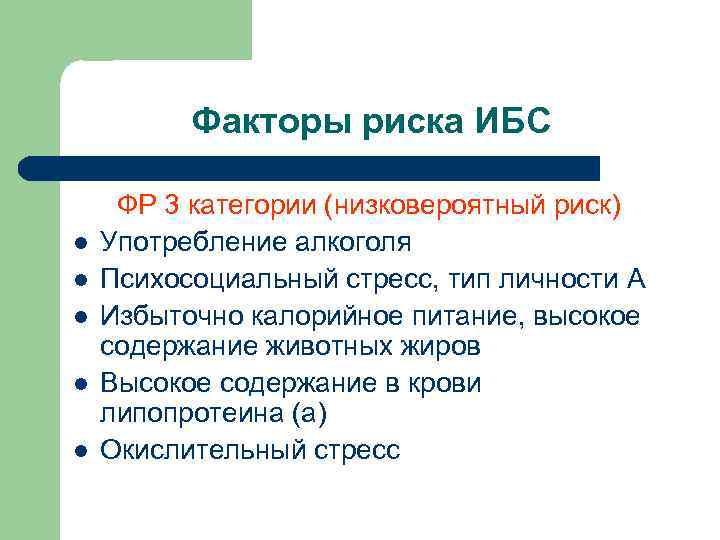

Факторы риска ИБС l l l ФР 3 категории (низковероятный риск) Употребление алкоголя Психосоциальный стресс, тип личности А Избыточно калорийное питание, высокое содержание животных жиров Высокое содержание в крови липопротеина (а) Окислительный стресс